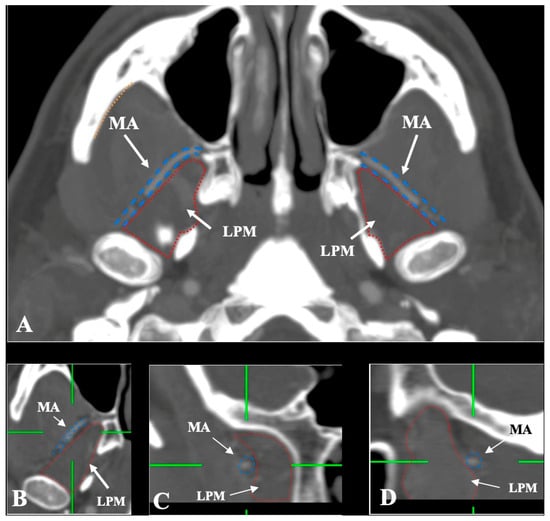

- Lateral (superficial) to the LPM: Detected in 321 sides (64.2%). This configuration was consistently visualized in axial, coronal, and sagittal planes (Figure 2).

- Medial (deep) to the LPM: Identified in 148 sides (29.6%), best appreciated on axial and coronal reconstructions (Figure 3).

- Intramuscular (transversing the LPM fibers): Found in 31 sides (6.2%), clearly depicted in all planes (Figure 4).